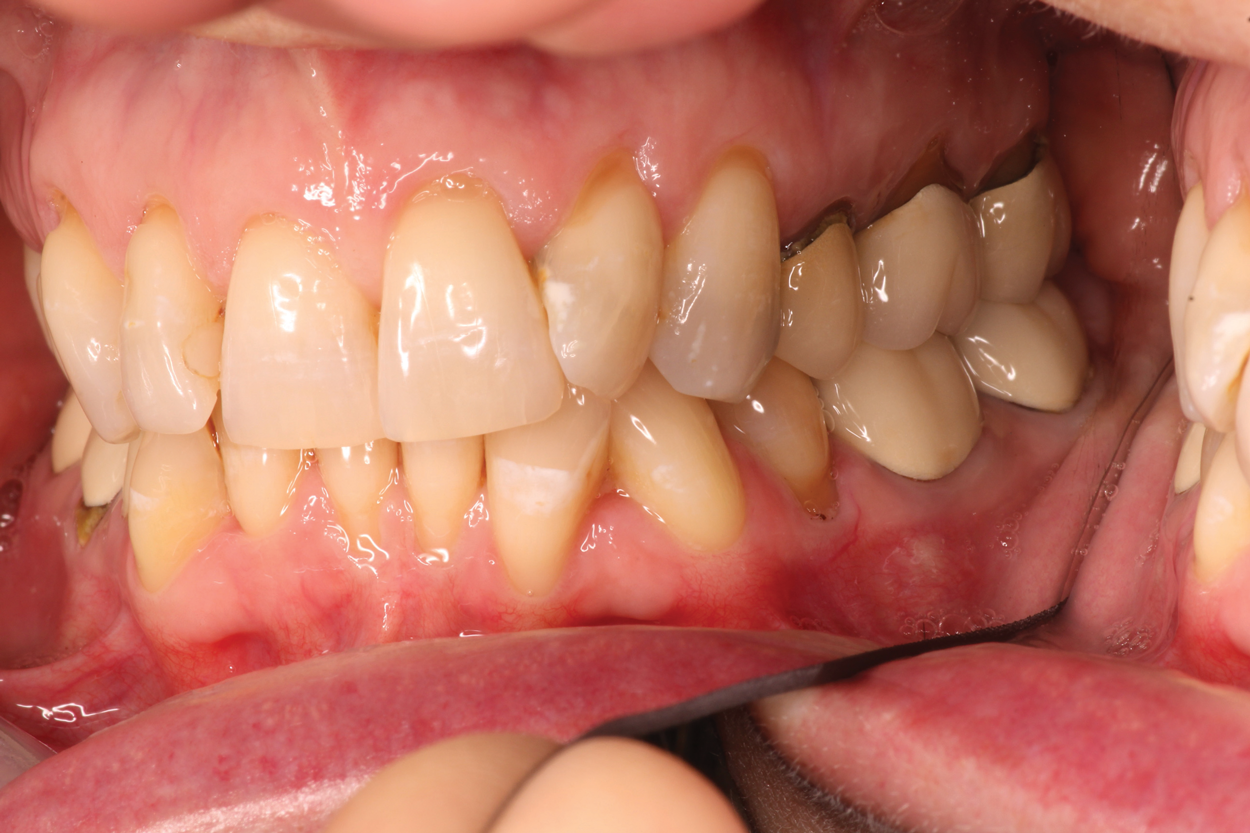

A 56-year-old female patient required an extensive treatment plan, including multiple crowns and fillings in each quadrant. She was able to complete treatment only in stages. By the time one quadrant was completed, she began to have pain on the mesial of tooth No. 20 (Figure 1 and Figure 2). Because the patient had no more dental benefits for the year, she needed to alleviate the sensitivity and prevent further problems between appointments. The doctor recommended SDF to stave off the sensitivity she was experiencing and to prevent growth of the lesion. Silver diamine fluoride was placed during a restorative appointment, and her sensitivity and pain subsided. When she returned a month later for her hygiene visit, she stated her pain had returned. A second SDF treatment was administered, which prevented the pain from returning a third time, until her restorative treatment could resume.

(1.) Patient exhbitied pain on the mesial of tooth No. 20.

Figure 1

(2.) Patient required an extensive treatment plan, including multiple crowns and fillings in each quadrant.

Figure 2